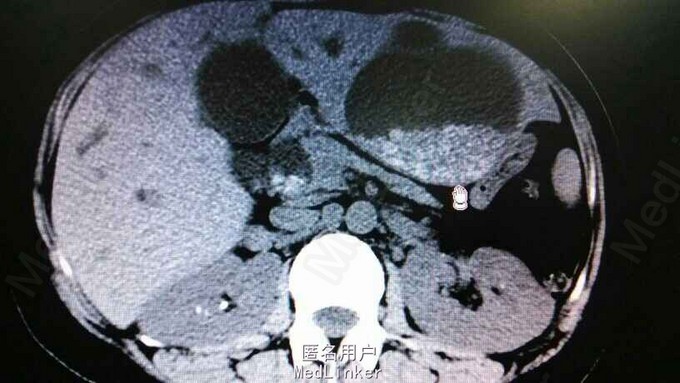

查体:右上腹轻压痛,无反跳痛,余无特殊。辅助检查,肝功,血象正常。腹部CT示肝内多发结石伴胆管囊状扩张。胆总管结石。见图